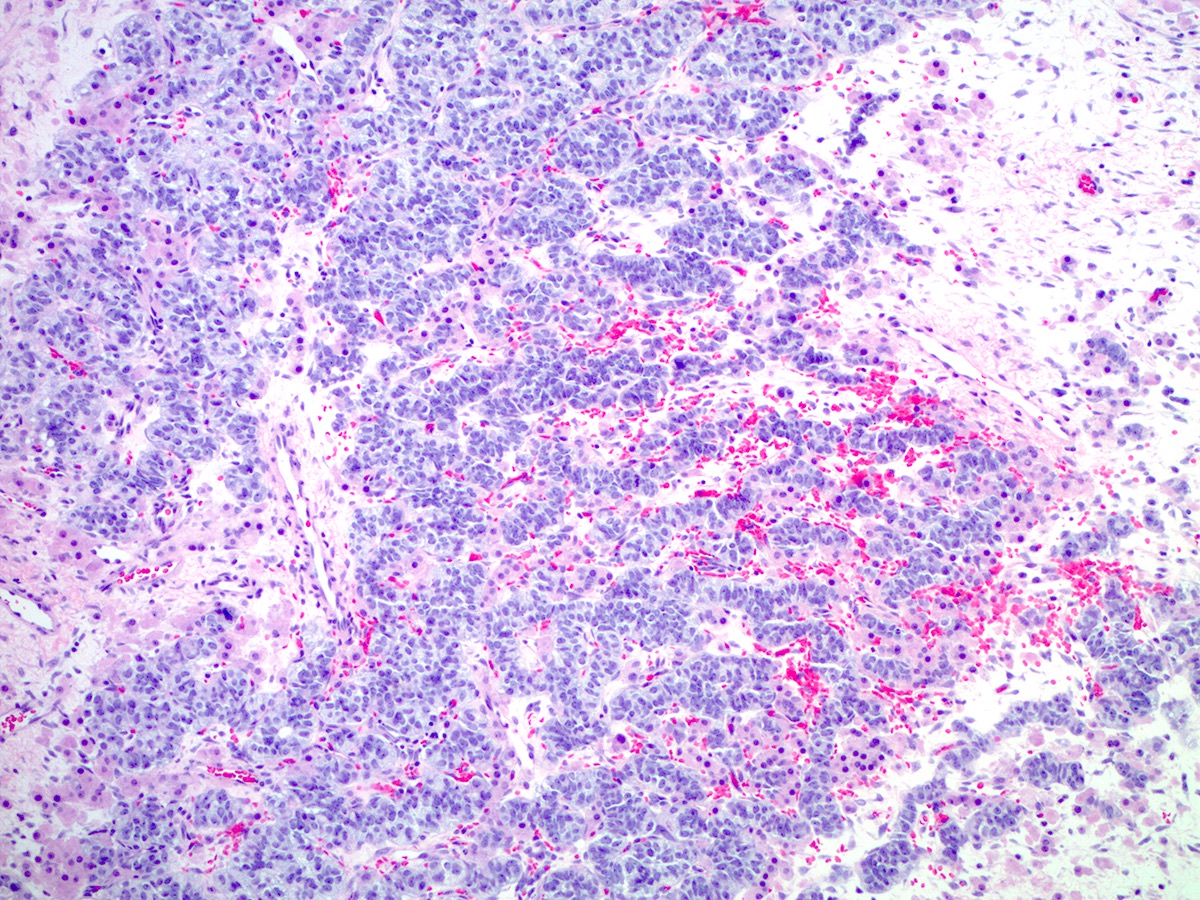

Microscopic (histologic) description

- Poorly differentiated

- Diffuse sheets of immature, sarcomatoid Sertoli cells with moderate to marked nuclear atypia and only rare foci of vague cord formation

- Increased mitotic activity, up to 20 mitoses per 10 high power fields

- Leydig cells are difficult to find; a few small clusters are typically located at the periphery of tumor nodules

Microscopic (histologic) images